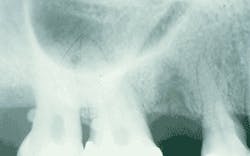

After a thorough clinical examination, periapical radiographs were ordered and exposed of all of the existing teeth in order to evaluate the periodontal condition. Examination of the right maxillary molar radiograph revealed the presence of two small round radiopacities - one attached to the root surface of tooth #2 and one attached to the root surface of tooth #3 (see radiograph). No bony expansion was noted in the area of the involved molars, and no additional radiopacities were noted on the other periapical films.

The enamel pearl may occur singly or in multiples. In most instances, one pearl occurs; however, up to four pearls have been identified on a single tooth. On a dental radiograph, the enamel pearl appears as a small round rediopacity attached to a root surface.